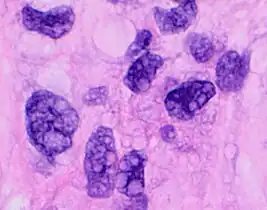

This can be done to slides processed by the chemical fixation or frozen section slides. To see the tissue under a microscope, the sections are stained with one or more pigments. The aim of staining is to reveal cellular components; counterstains are used to provide contrast.

The most commonly used stain in histology is a combination of hematoxylin and eosin (often abbreviated H&E). Hematoxylin is used to stain nuclei blue, while eosin stains the cytoplasm and the extracellular connective tissue matrix of most cells pink. There are hundreds of various other techniques which have been used to selectively stain cells. Other compounds used to color tissue sections include safranin, Oil Red O, congo red, silver salts and artificial dyes. Histochemistry refers to the science of using chemical reactions between laboratory chemicals and components within tissue. A commonly performed histochemical technique is the Perls' Prussian blue reaction, used to demonstrate iron deposits in diseases like Hemochromatosis.[2]

Recently, antibodies have been used to stain particular proteins, lipids and carbohydrates. Called immunohistochemistry, this technique has greatly increased the ability to specifically identify categories of cells under a microscope. Other advanced techniques include in situ hybridization to identify specific DNA or RNA molecules. These antibody staining methods often require the use of frozen section histology. These procedures above are also carried out in the laboratory under scrutiny and precision by a trained specialist medical laboratory scientist (a histoscientist). Digital cameras are increasingly used to capture histopathological images.